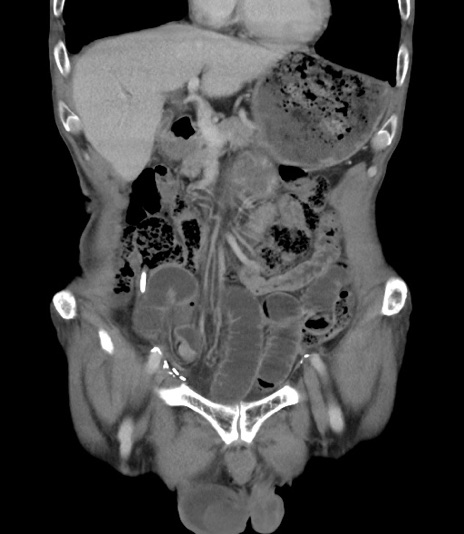

症例3(冠状断像)

【症例】 70歳代男性

【主訴】右鼠径部腫瘤、疼痛

【現病歴】本日朝より上記主訴あり、受診。

【既往歴】膀胱癌にて膀胱全摘、両側尿管皮膚瘻

【データ】WBC 5600、CRP 0.56